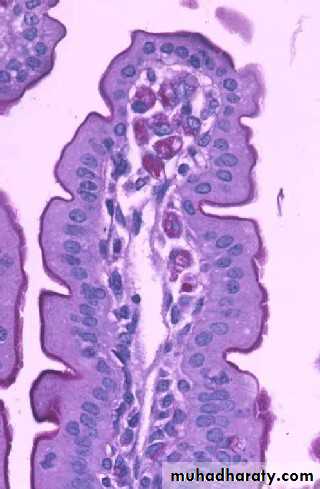

Eosinophils

Bilobed nucleusBright pink Granules

Function:

Important in allergic rxns, parasitic infections, and phagocytosis of Ab-Ag complexes